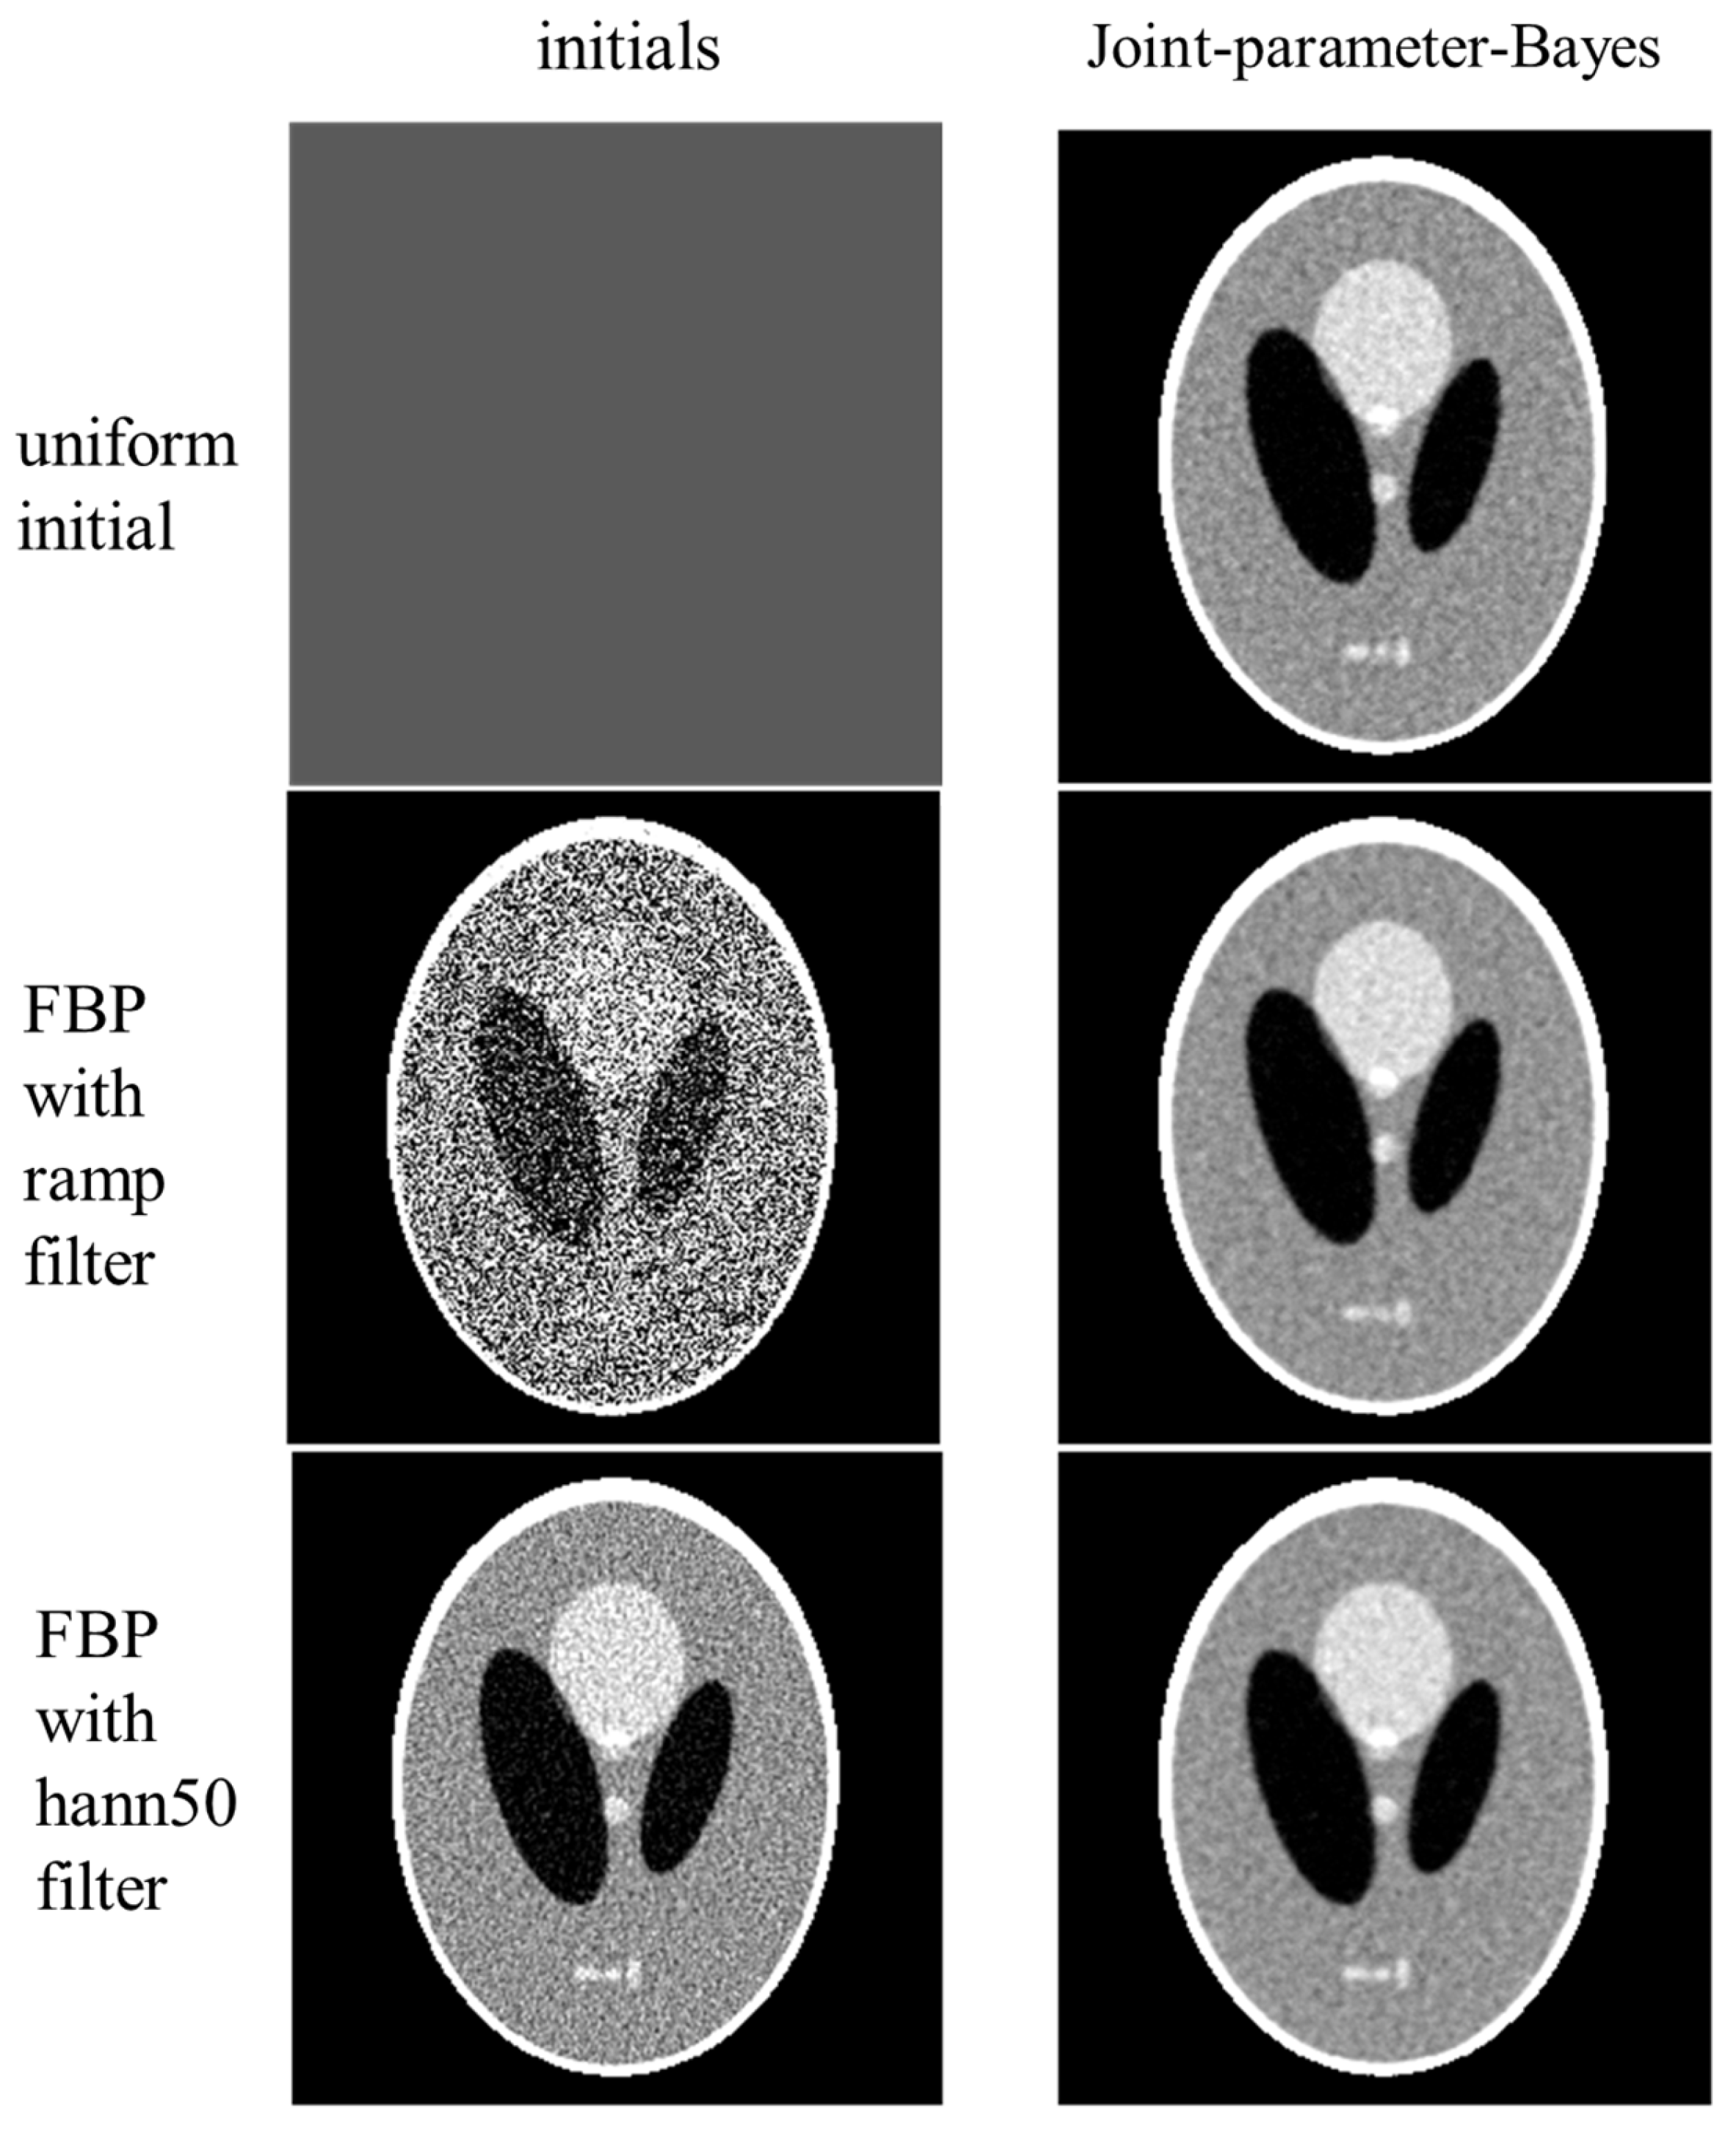

We further investigated the effect of initialization on the proposed joint-parameter-Bayes method. Three different initials were tested: uniform initial by averaging the FBP results, FBP with ramp filter, and FBP with hann50 filter. We investigated the effect on the Poisson-like signal-dependent noise to post-log sinogram data. This simulation provides the opportunity to deal with the signal-dependent noise data, where the signal variance is known to equal its signal mean. This means that the true value of is . First, we used the true variance for , instead of the estimated and just varied the initials. The reconstructed images and their initials are presented in Figure 6. The estimated parameters along the iterations are presented in Figure 7. According to Figure 7, the pattern of does not change too much for different initials, but the pattern of varies. Their ratio follows a similar pattern with a different convergence rate. According to Figure 6, the reconstructed results are stable with all three different initials. This implies that joint-parameter-Bayes can effectively estimate the parameter values starting with different initials and provide stable solutions anyway when knowing the true variance.

Figure 6.

Performance of joint-parameter-Bayes with different initials. From top to bottom, the initials (left column) are uniform averaged from FBP, FBP with ramp filter, and FBP with hann50 filter, while the corresponding joint-parameter-Bayes reconstructions are shown on the right (right column).